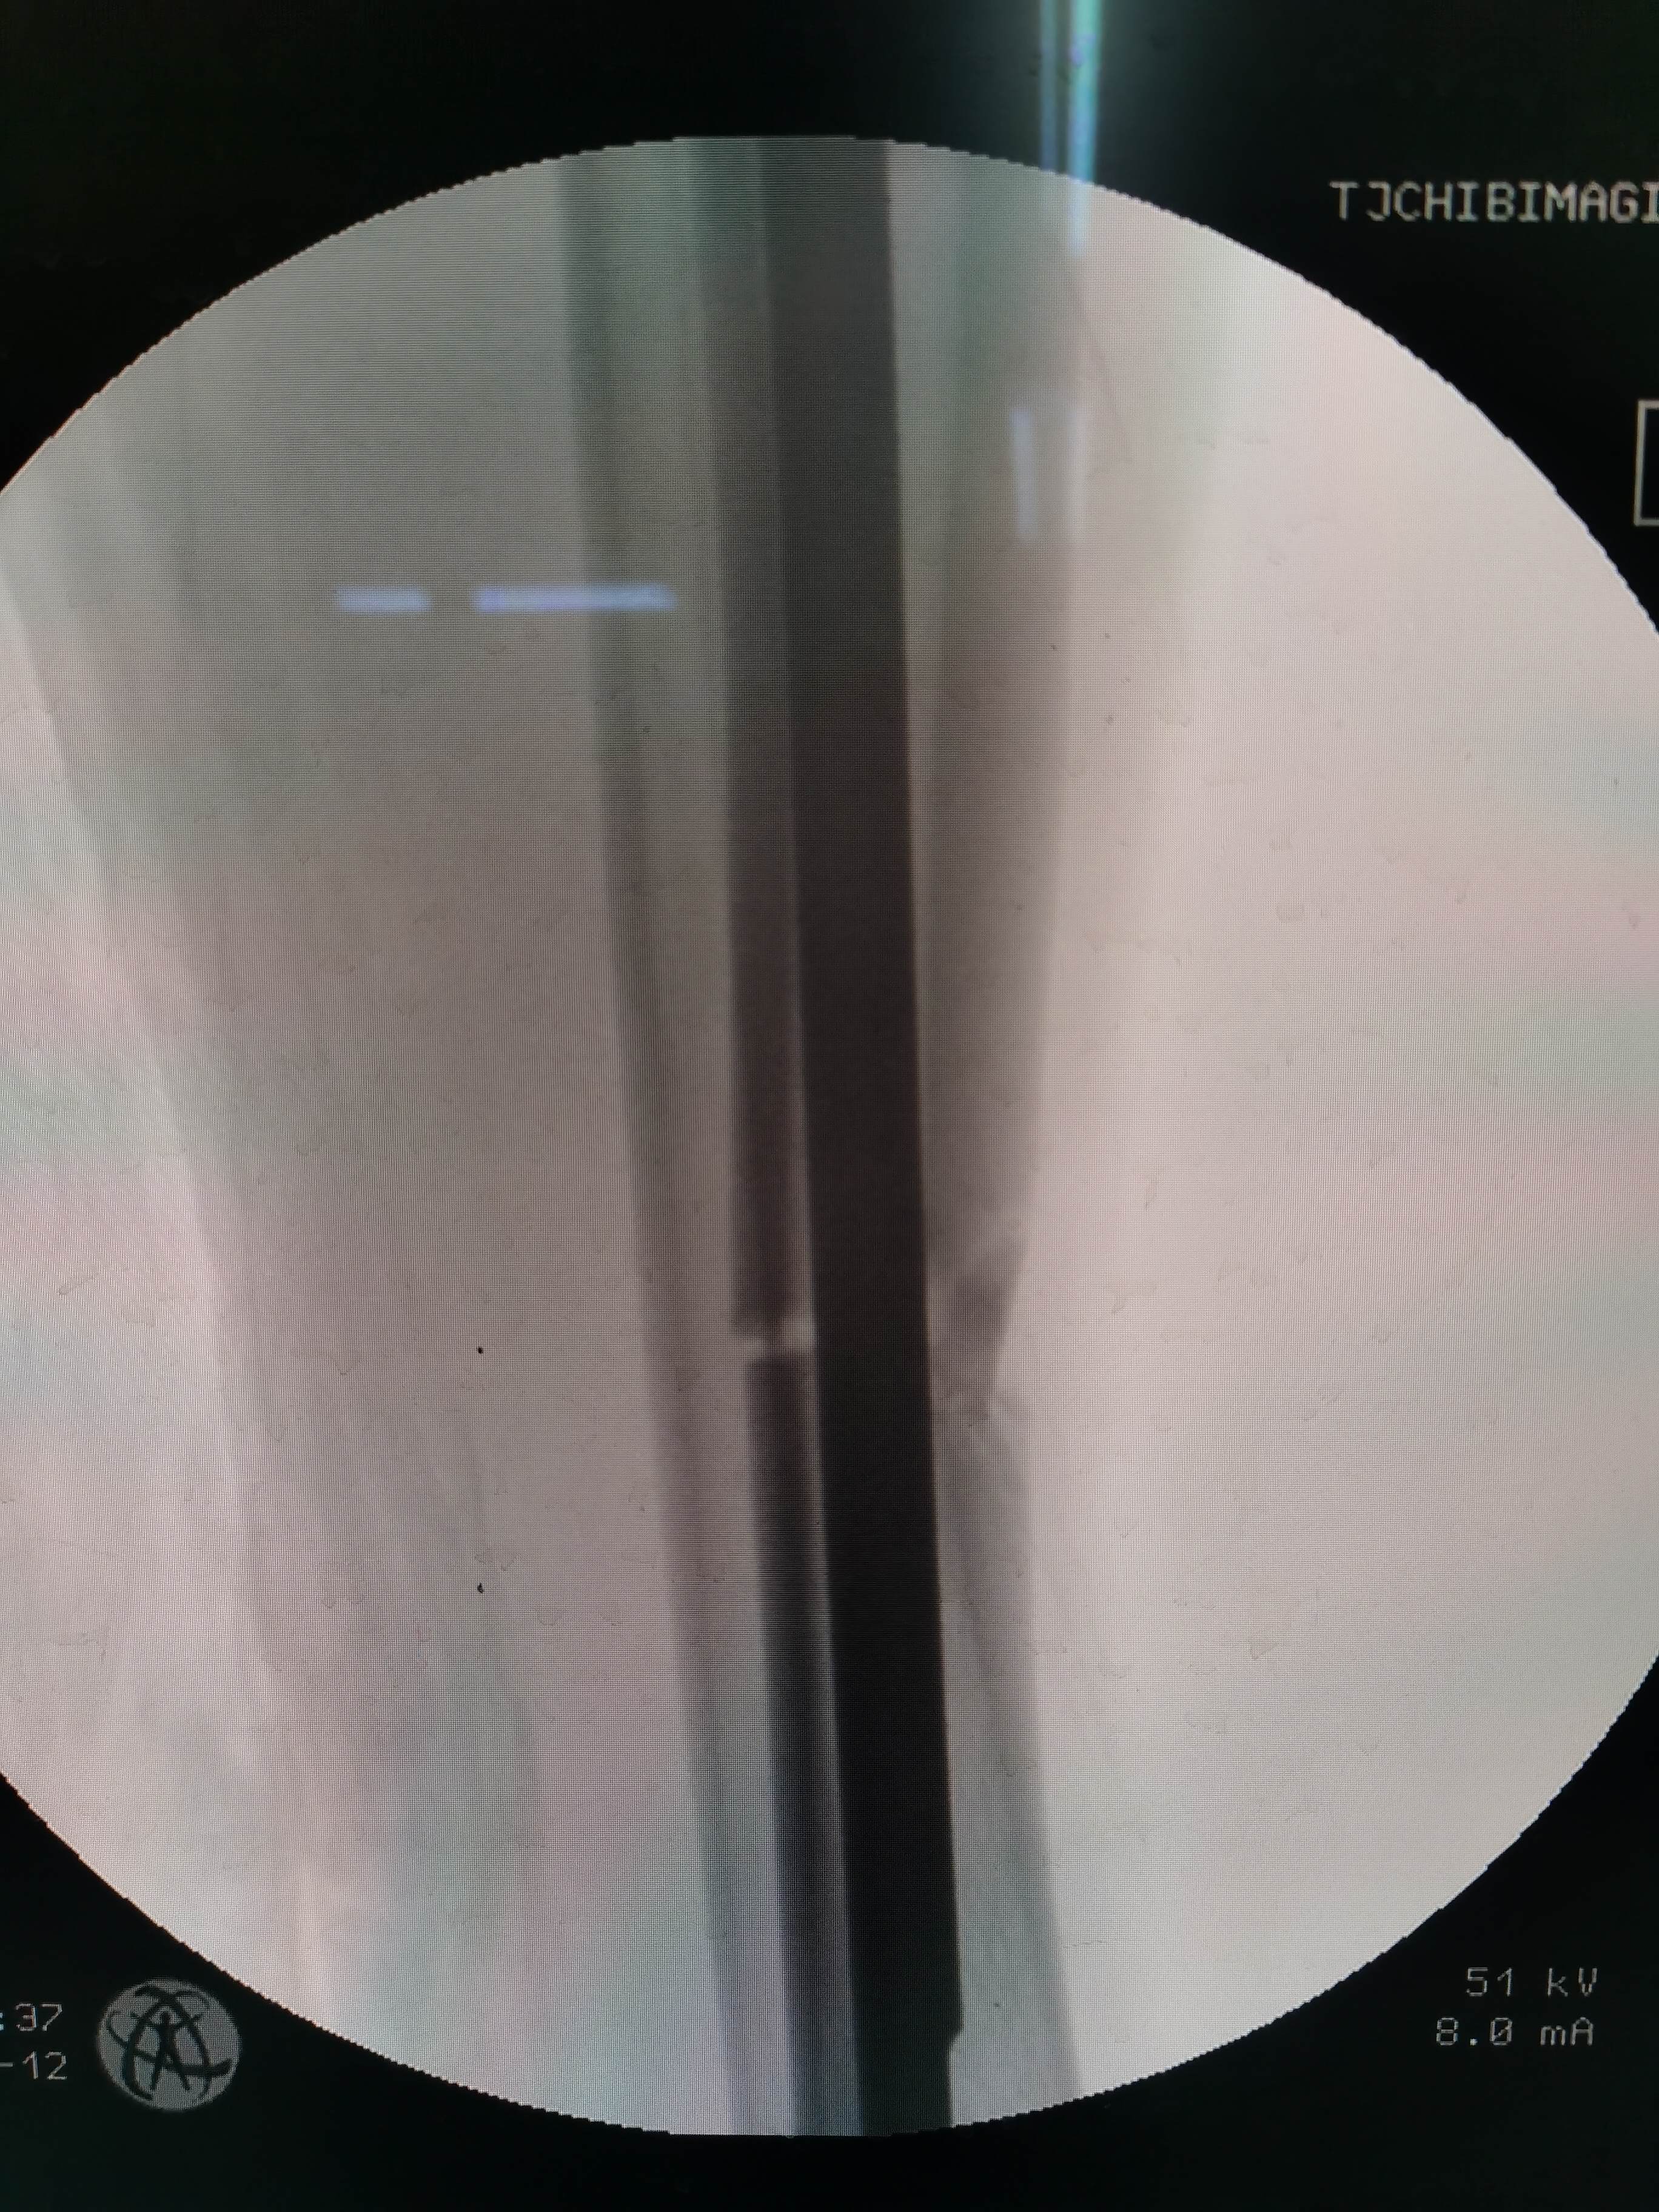

术中透视骨折端正位

术中透视骨折端侧位

患者男,53岁,因外伤致右胫骨中段粉碎性骨折。内踝前方有片状皮肤擦伤。入院后完善术前检查,给予石膏托固定,消肿处理。评估手术风险后,在腰硬联合麻醉下行右胫骨骨折闭合复位交锁髓内钉固定。术中屈曲膝关节,传统髌韧带入路,锥形开口后置入导针,金手指插入复位,扩髓,植入10mmx340mm髓内钉,远近端锁钉。手术顺利,因盲打远端锁钉,反复调整了几次,手术时间一个半小时,未使用止血带,出血约100m1。